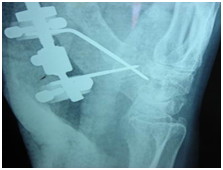

After an open debridement of the first carpometacarpal joint (Figure 2) we apply, under x-ray control, a mini ex-fix system3,5 (Figure 3).

Figure 2 After an open debridement of the first carpometacarpal joint.

Figure 3 Under x-ray control, a mini ex-fix system.

It’s very important the application of the first needle of the system to cause compression between the base of the first metacarpal and the trapezium (Figure 4 & 5).6-10

Figure 4 Under x-ray control, a mini ex-fix system.

Figure 5 Under x-ray control, a mini ex-fix system.